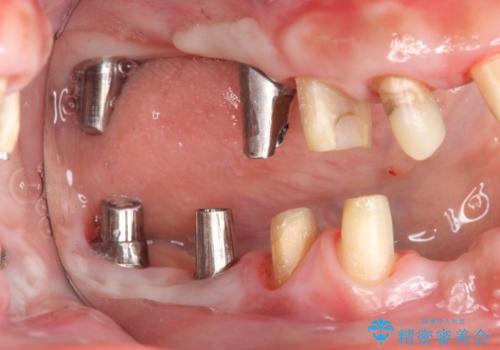

セラミック・インプラント治療を含む包括歯周病治療

- 「銀歯だらけの歯を変えたい。他院で歯周病と指摘されたがクリーニング以外何もしてくれない。」、とセラミック治療歯周病治療を希望され来院されました。

検査の結果、感染根管や欠損、歯周病により残すことのできない歯、等多々問題が認められます。

残すことのできる歯できない歯を選別し、欠損部にはインプラントによる咬合機能の回復、保存できる歯には歯周病治療・根管治療を行う治療計画としました。